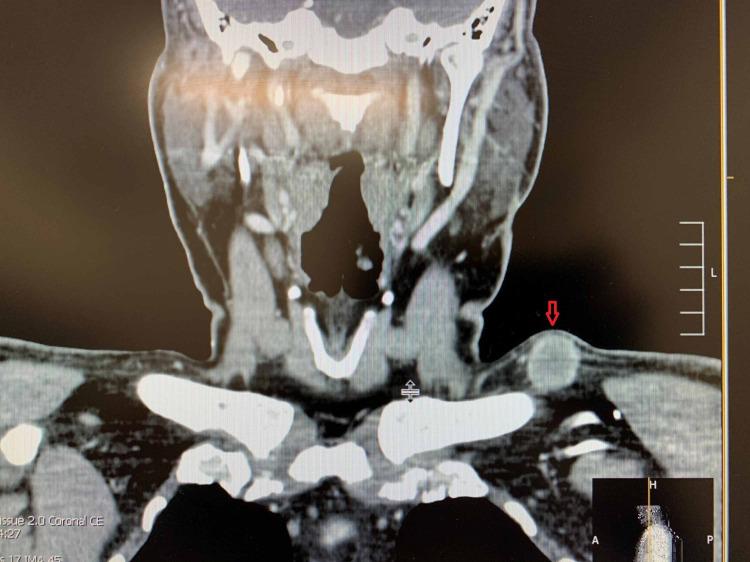

Pembrolizumab is an immune checkpoint inhibitor approved for use in many cancer types such as non-small cell lung cancer (NSCLC), metastatic melanoma, head and neck cancers, hepatocellular carcinoma, and renal cell carcinoma. There are many reported cases of patients on immunotherapy who have discontinued treatment due to the development of immune-related adverse effects (irAE). Recognition of the histopathologic patterns of dermatologic toxicities due to immunotherapy will become increasingly important for ensuring appropriate management and optimal patient care. Here, we present a case of a 72-year-old man with metastatic carcinoma of unknown primary origin treated with pembrolizumab who developed an immune-related cutaneous adverse event (ircAE) in the form of lichenoid dermatitis.

帕博利珠单抗是一种免疫检查点抑制剂,已被批准用于多种癌症类型,如非小细胞肺癌(NSCLC)、转移性黑色素瘤、头颈癌、肝细胞癌和肾细胞癌。有许多关于接受免疫治疗的患者因出现免疫相关不良反应(irAE)而停药的报道病例。认识免疫治疗引起的皮肤毒性的组织病理学模式对于确保适当的管理和最佳的患者护理将变得越来越重要。在此,我们报告一例72岁男性患者,其原发灶不明的转移性癌接受帕博利珠单抗治疗后出现了苔藓样皮炎形式的免疫相关皮肤不良事件(ircAE)。